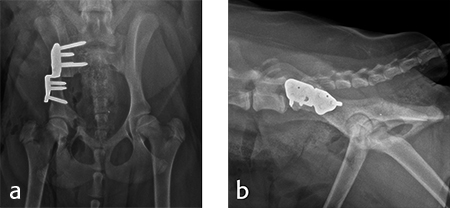

For each surgical procedure, the patient was placed in dorsal recumbency to enable the pubic ostectomy. The patient was repositioned in lateral recumbency to perform the DPO. A left ilial osteotomy was performed caudal to the sacrum. A 25° DPO/TPO plate was attached to the caudal ilial segment using locking 3.5 mm screws in the three stacked combi holes. The caudal acetabular segment was rotated laterally until the cranial aspect of the plate was in contact with the lateral aspect of the cranial ilial segment. The osteotomy site was compressed and the plate was secured to the cranial ilial bone segment using a 3.5 mm cortical screw in the LCP combi hole in the cranial side of the plate. Three additional 3.5 mm locking screws were placed in the remaining stacked combi holes in the cranial segment of the plate (Fig 9).

Activity was restricted to leash walks for 6 weeks postoperatively. The radiographic examination 1 month after each surgery revealed partial healing of the ilial osteotomy and stable implants. Postoperative radiographs at 6 months after both surgical procedures revealed complete healing of the ilial osteotomies, stable implants, and excellent coxofemoral conformation, with no subluxation of the femerol head. Mild osteoarthritis was observed, however. At both the 4 and 6 month evaluation, the dog was using both hind limbs without any evidence of lameness and was showing no signs of instability or pain of either hip (Fig 10).